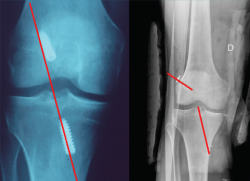

El estudio radiológico recomendado debería incluir proyecciones anteroposteriores y laterales, axiales de rótula, telemétricas de la extremidad inferior y también en posición de Schuss (en carga y con unos 30° de flexión de la rodilla). La radiología simple va a permitir identificar qué técnica quirúrgica se realizó inicialmente y qué material se utilizó para la fijación (Figura 1). La proyección en Schuss permite observar si existen cambios degenerativos en los compartimentos femorotibial interno o externo de la rodilla de forma más precisa que con la radiología simple en decúbito supino. Finalmente, la radiografía telemétrica de las extremidades inferiores va a permitir conocer el eje mecánico de la extremidad. La existencia de deformidades en el plano coronal se ha asociado a un incremento de la solicitación mecánica del LCA y también del riesgo de rotura de la plastia (Figura 2)(21).

Figura 2. Paciente de 21 años con antecedente de reconstrucción anatómica del ligamento cruzado anterior (LCA) y ángulo posteroexterno que requirió cirugía correctiva de un genu varo de 7° después de fracasar la reconstrucción ligamentosa.

Pendiente tibial y deformidad en el plano coronal

La pendiente tibial posterior se considera un factor importante a tener en cuenta en los casos de fracaso de la reconstrucción del LCA(35,36). Se ha asociado en numerosos trabajos un incremento de la pendiente tibial por encima de los 10-12° con un aumento de las solicitaciones mecánicas sobre el LCA, tanto nativo como después de su reconstrucción, por lo que se considera un factor a tener en cuenta en los casos de fracaso de la reconstrucción del LCA(37,38,39,40,41,42). En esta línea, algunos autores han atribuido un mayor valor como factor de riesgo a la pendiente tibial posterior del compartimento externo, por su mayor repercusión sobre la estabilidad rotacional de la rodilla(43,44).

Independientemente de las deformidades en el plano axial, las deformidades en el plano coronal, sobre todo el genu varo, se han relacionado también con un incremento de las solicitaciones mecánicas sobre el LCA y secundariamente como factor de riesgo de rotura(45,46).